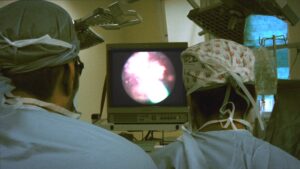

内臓も眼球も無修正で全部見せる!医者の愚痴まで丸聞こえの解剖ドキュメンタリー『人体の構造について』